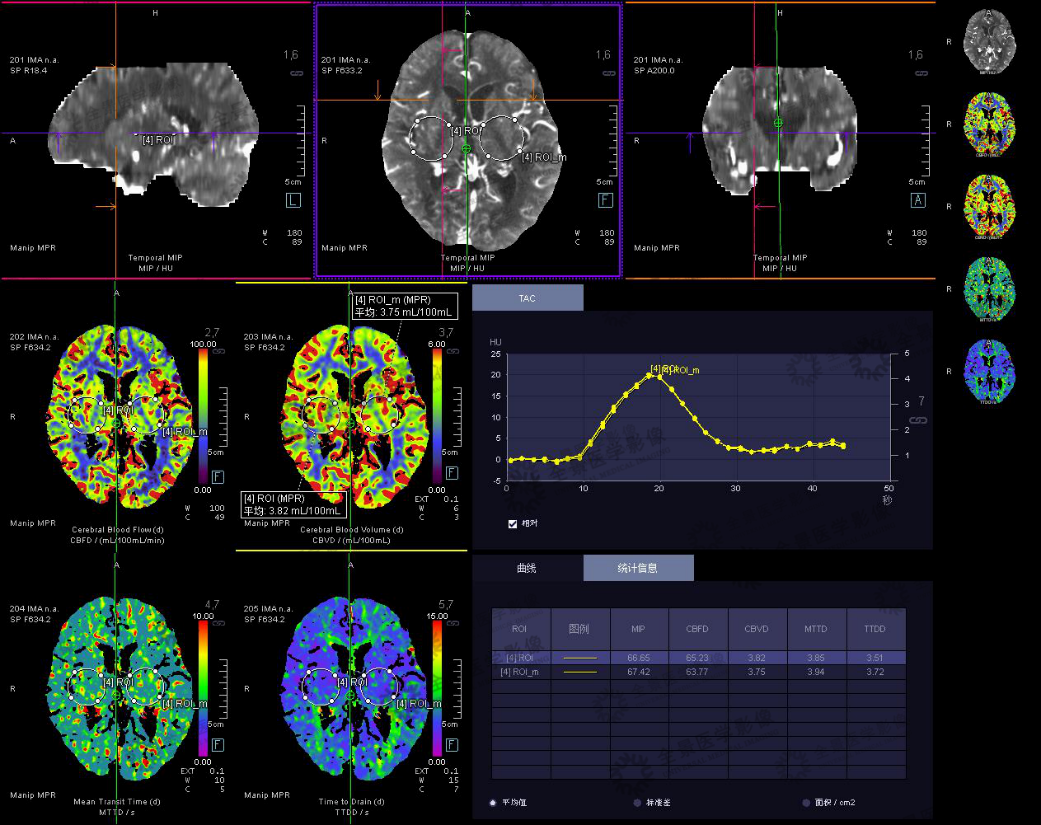

病史:男,79岁,怀疑早期脑缺血病变行颅脑灌注成像,如图所示:

颅脑灌注成像示脑实质内未见明显异常灌注区,于双侧大脑半球对称位置分别选取ROL,分别为ROL、ROL-m。ROL的CBF、CBV、MTT、TTD值分别为65.23、3.82、3.85、3.51,ROL-m的CBF、CBV、MTT、TTD值分别为63.77、3.75、3.94、3.72。双侧ROL区域相应参数数值均未见明显差异。动态增强的时间-信号强度曲线中,ROL与ROL-m及相同层面的平均值未见明显差异。

注:CBF-脑血流量;CBV-脑血容量;MTT-平均通过时间;TTD-延迟时间;TTP-达峰时间

结果:脑灌注成像未见明显异常。